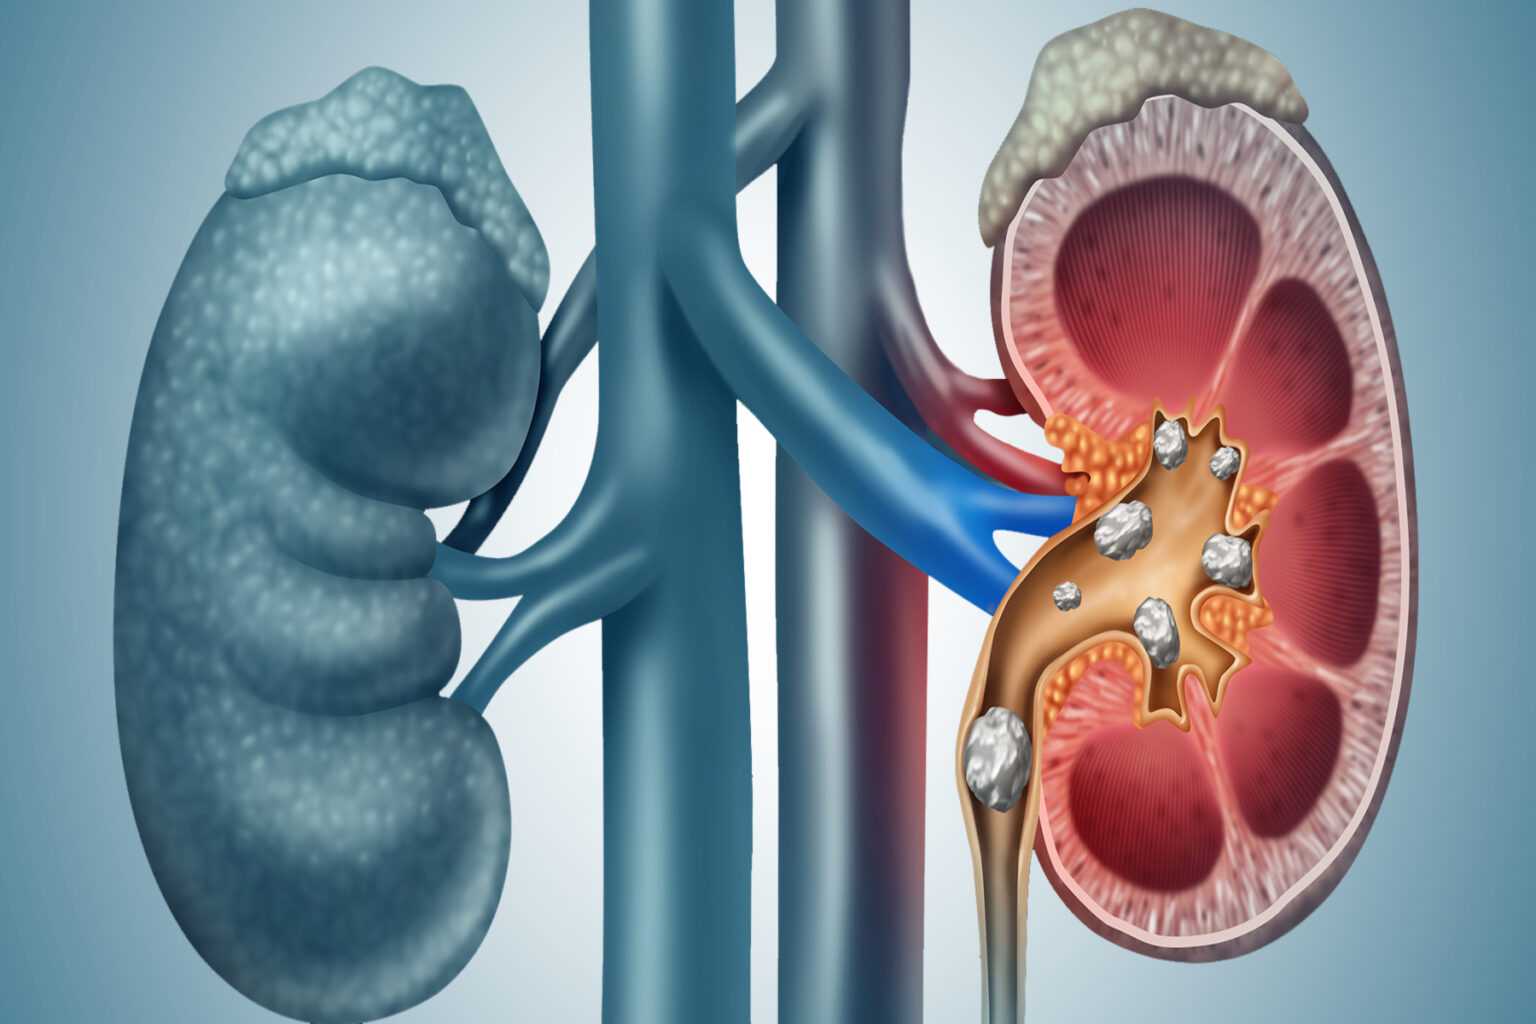

Μια νέα θεραπεία με υπερήχους για τις πέτρες στα νεφρά μπορεί να προσφέρει ανακούφιση χωρίς πόνο όσο ο ασθενής είναι ξύπνιος, λένε οι ερευνητές. Οι πέτρες στα νεφρά είναι συχνά βασανιστικά επώδυνες. Στις περισσότερες περιπτώσεις, οι ασθενείς καλούνται να το βγάλουν, μερικές φορές για εβδομάδες, με την ελπίδα ότι η πέτρα θα περάσει τελικά από το ουροποιητικό σύστημα – από το νεφρό στην ουροδόχο κύστη – μόνη της. Αλλά για περίπου έναν στους τέσσερις ασθενείς αυτό δεν συμβαίνει ποτέ, προκαλώντας χειρουργική επέμβαση.

Πέτρες στα νεφρά